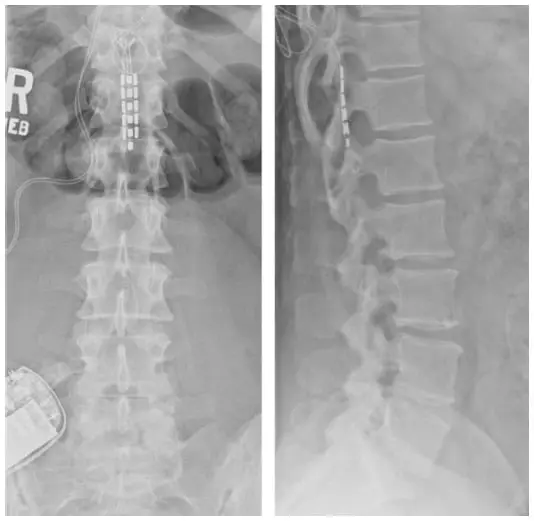

Intrathecal Baclofen Pump is inserted by an experienced spine surgeon in Chennai, India to treat severe spasticity. The pump can be filled with Baclofen (Spasticity) or Morphine (Pain). Indications of Baclofen Pump are: